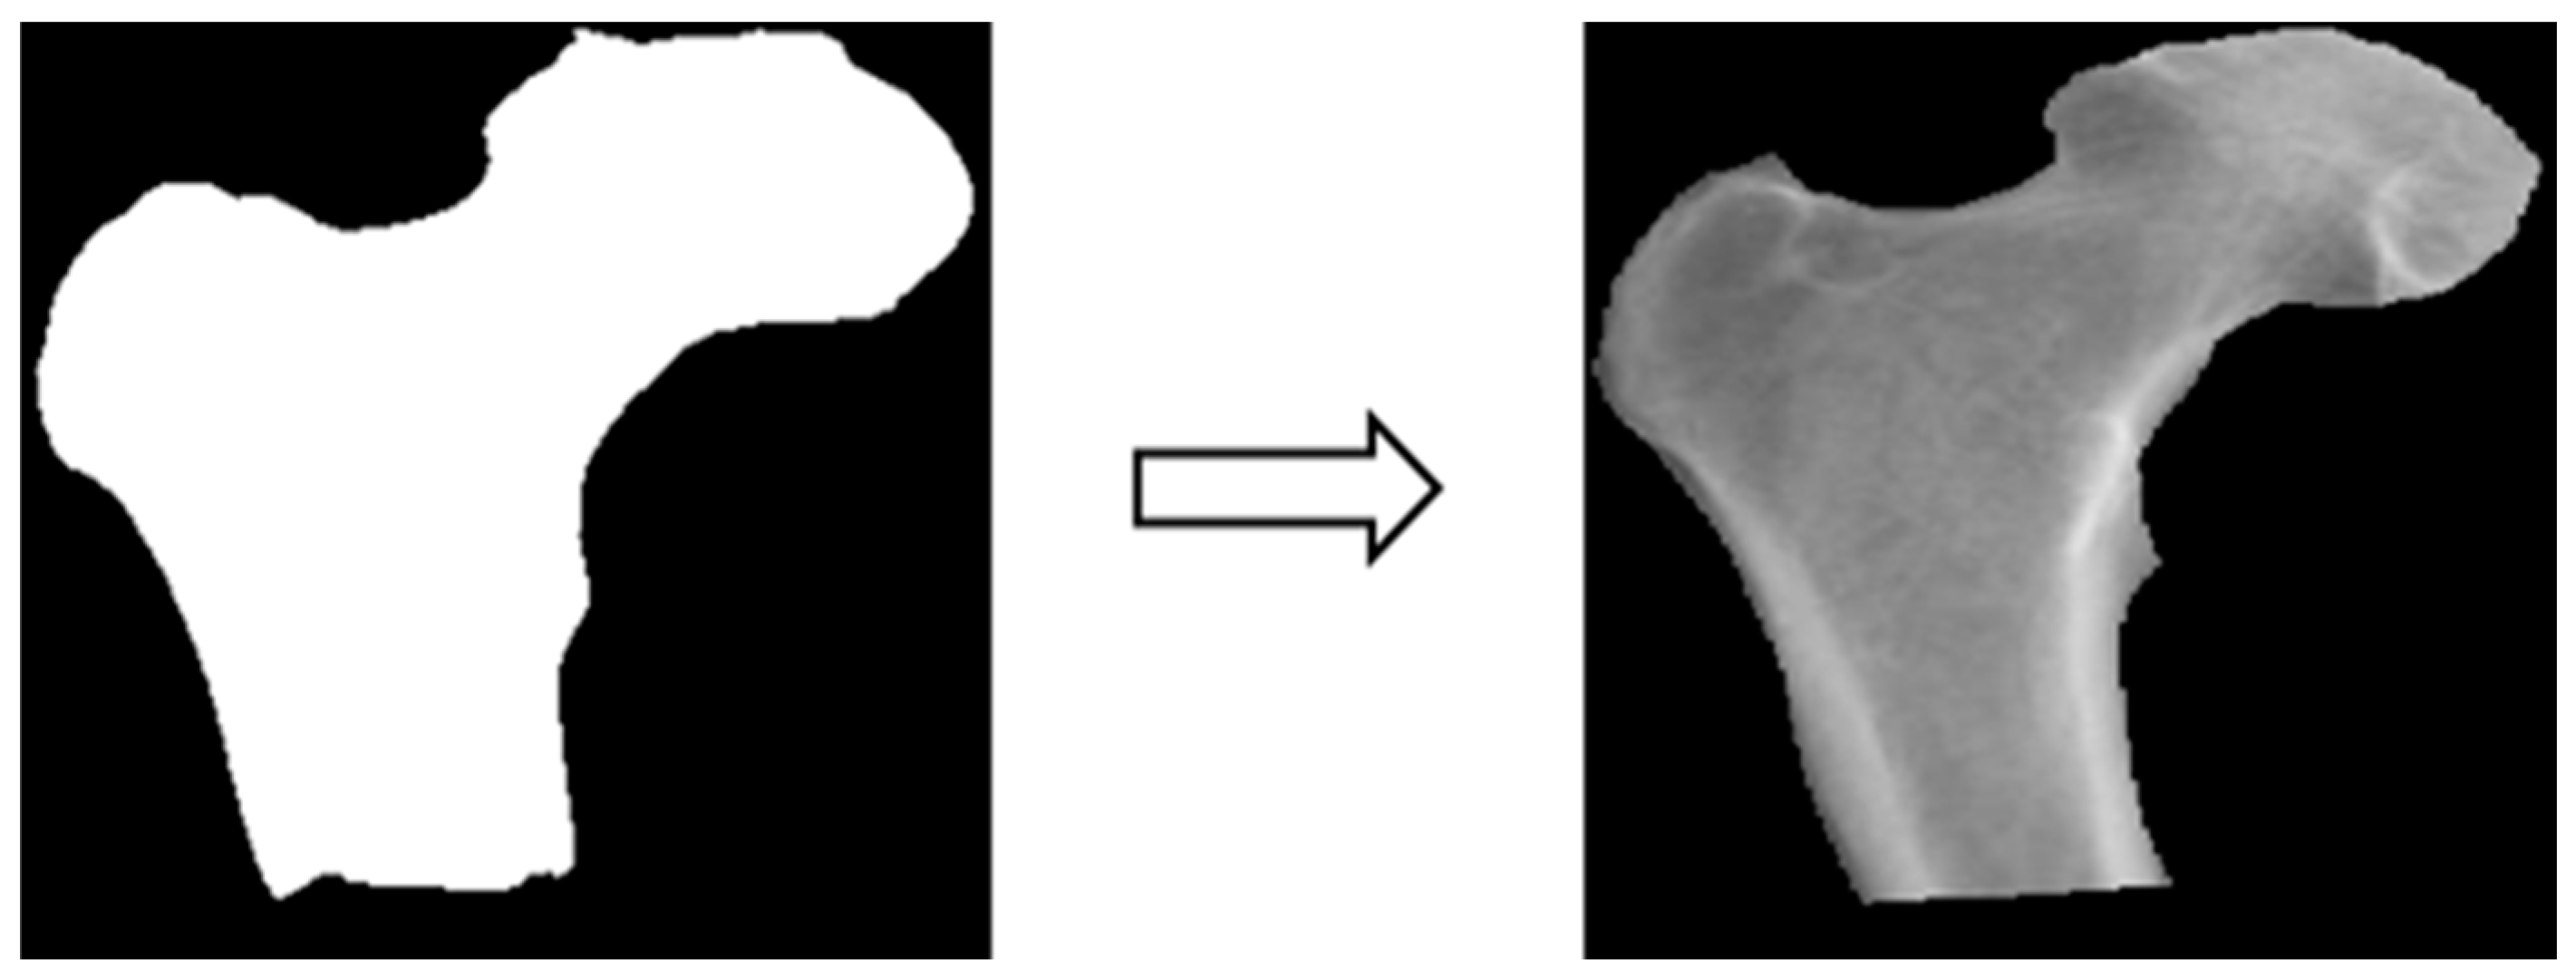

3.3.3. Image matting

Based on the four parts of the image segmentation of the binary image and the original X-ray image together, the original X-ray image only retains the part of the image segmentation as shown in Figure 4; the other non-part of the contour of the background to remove, the image de-behind the hope that it can enhance the accuracy of the classification of the depth of the learning process, and then the image classification will be segmented images and not segmented images will be compared.